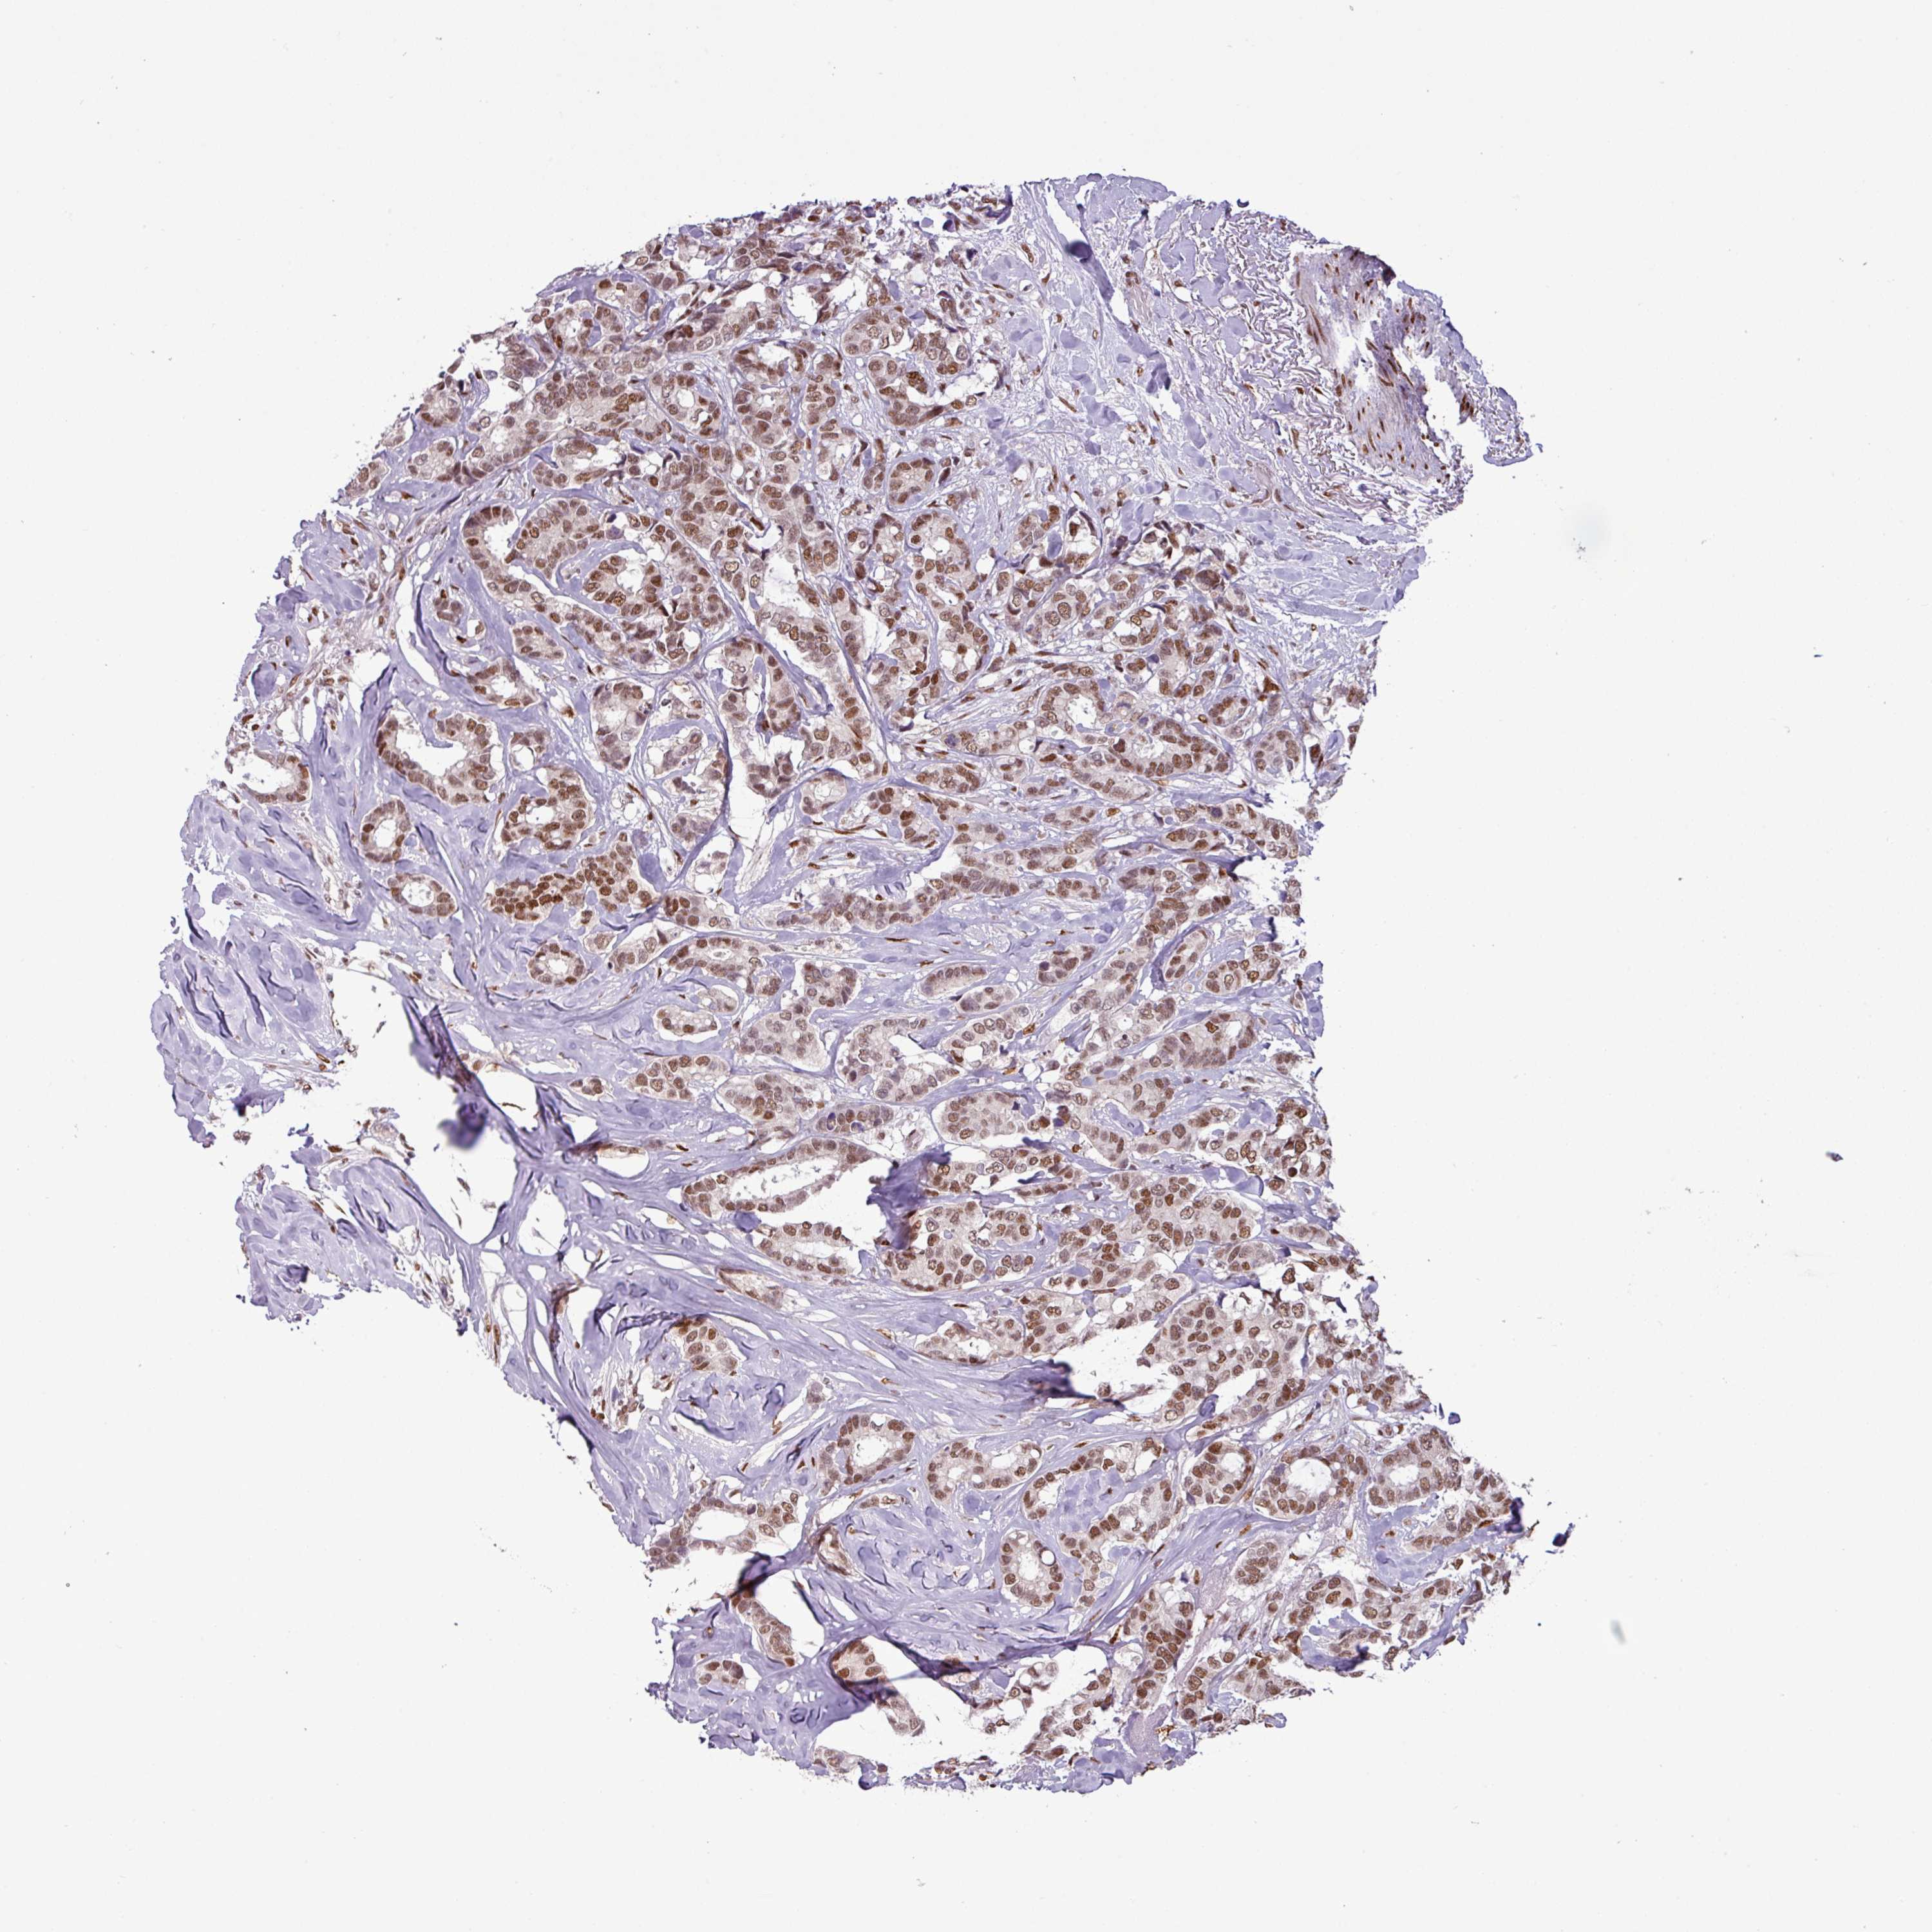

BRCA TCGA BRCA VALIDATION PROTEIN EXPRESSION

ANTIBODIES

AND

VALIDATION